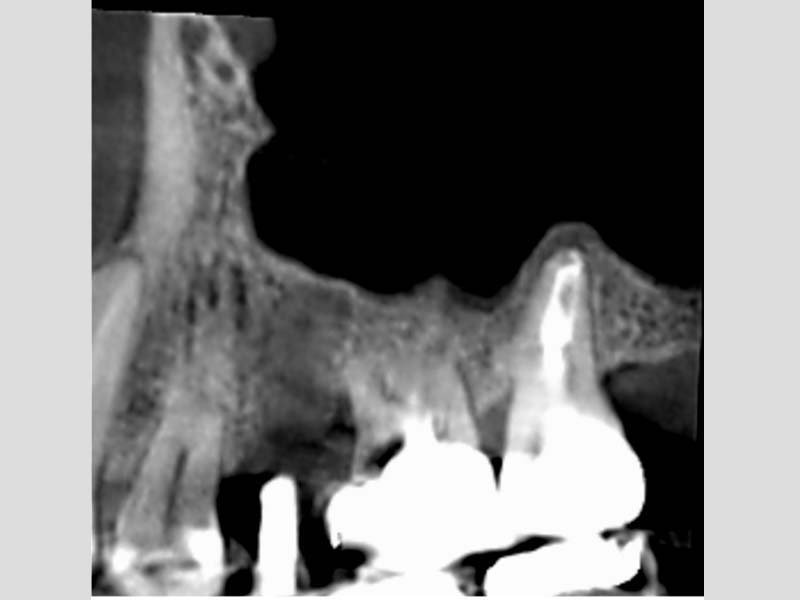

術後的電腦斷層,比竇黏膜已完全復原

術前 / 術後